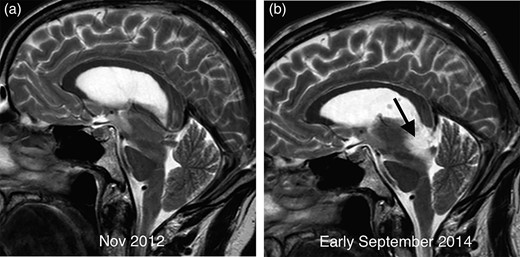

The patient underwent a series of four MRI scans between 2012 and 2015. The first MRI performed in November 2012, which had erroneously been reported as normal, shows downward brainstem displacement (Fig. 1a). Of note, subdural collections and meningeal enhancement were absent. A second MRI performed in early September 2014 revealed a moderately expansile lesion occupying the posterior aspect of the midbrain (Fig. 1b).

Comparative sagittal T2 imaging performed 2 years apart in demonstrating sagging of the brainstem with elongation of the midbrain and marked flattening of the pons surface. The scan from early September 2014 (b) demonstrates a new T2 hyperintense mass in the midbrain (arrow) compared with the earlier image (a).